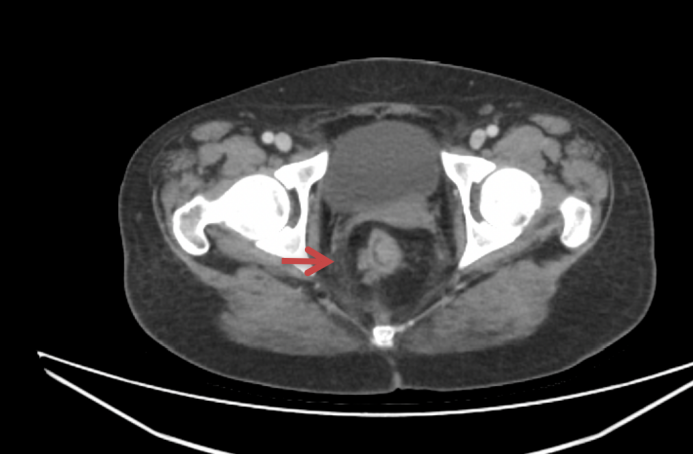

增强CT:可见直肠中上段肠壁增厚,考虑ca,盆腔多发淋巴结肿大,疑转移。

增强MRI:可见直肠肿物,侵及肠壁全层,肠壁外有多发肿大淋巴结。考虑直肠癌(T3N2Mx)。

(4)患者停药4个月后常规复查发现双肺新发结节,左侧盆壁侧方有肿大淋巴结。2019.03.06 增强CT如下,同时肿瘤标志物cea升高至7.83ng/ml。考虑肿瘤复发。